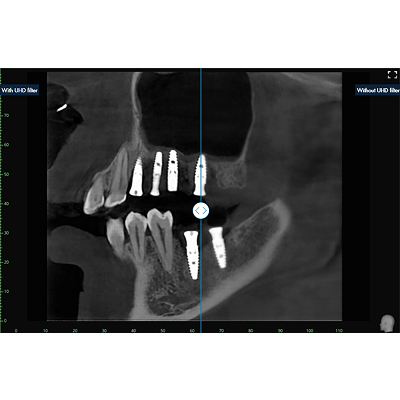

UHD Filter powered by AI

The UHD filter adjusts the brightness and contrast of the X-ray image individually and dynamically in different image areas. The result is an optimized X-ray image that enables clear and precise diagnostics. The filter is available for intraoral, panoramic, ceph and 3D/CBCT images.